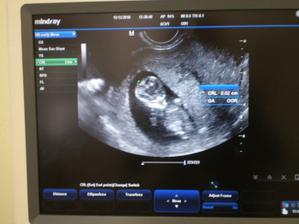

Nase babatenko krasne